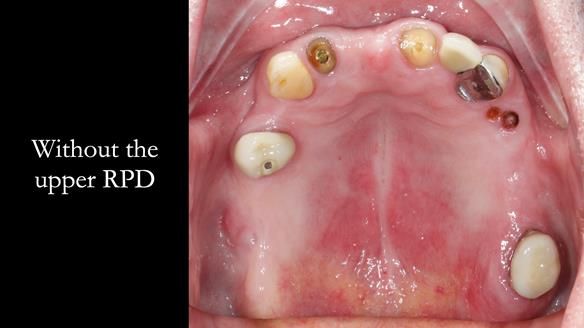

This edition features the case of Edgar, who sought help for a poorly fitting, acrylic-based partial denture that rocked, affected his speech, and caused discomfort. After considering various treatment options, including dental implants, Edgar opted for a metal-based removable partial denture, designed by myself with input from my technician, Rowan Garstang.

Treatment Process: I provided the clinical work while Rowan Garstang delivered the technical aspects. The treatment required fifteen visits to fit and review Edgar.